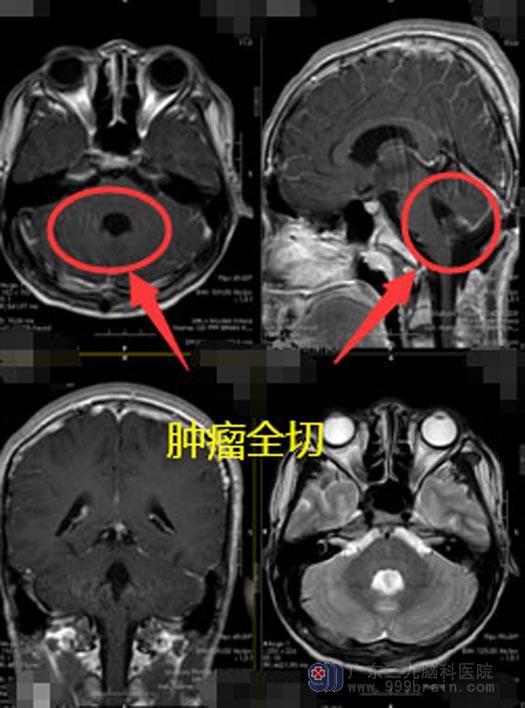

为明确病情,结合铭铭的病史、临床症状及影像表现,鲁明邀请了肿瘤科医生进行联合会诊。经过讨论分析、鲁明建议术前辅助局部放疗,减少肿瘤负荷后再行下一步治疗。经过9Gy/5f术前放疗后,铭铭的头痛、呕吐的情况好转。放疗结束,手术指征明确,完善相关检查后,神经外五科团队携手为铭铭在全麻下行“四脑室占位性病变切除术+左顶枕硬膜下血肿钻孔引流术”,手术过程顺利。

术后加强治疗,予以脱水降颅压、止血、控制感染、维持内环境稳定、对症及支持治疗。目前铭铭恢复良好、头痛、呕吐的症状已经消失,已经可以下床活动了。